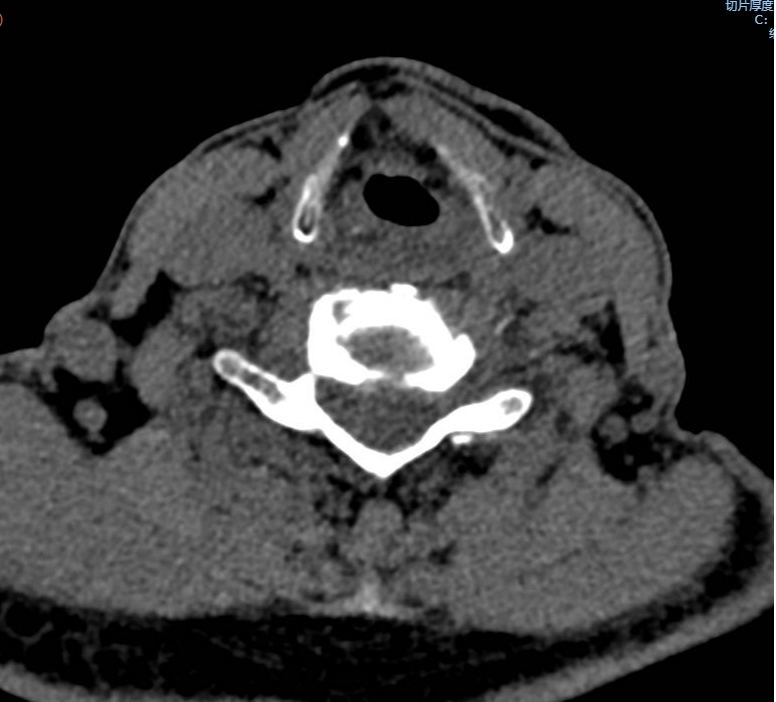

手術(shù)之后3天,黃大伯疼痛得到很好緩解,露出了許久沒有的笑容,終于可以安心躺著睡覺了,1個月后基本恢復(fù)了正常生活,6個月后復(fù)查CT發(fā)現(xiàn)突出的頸椎間盤已經(jīng)基本消失了,黃大伯一家人對治療效果非常滿意。

手術(shù)之前CT,巨大突出物 術(shù)后6個月復(fù)查CT:突出物消失